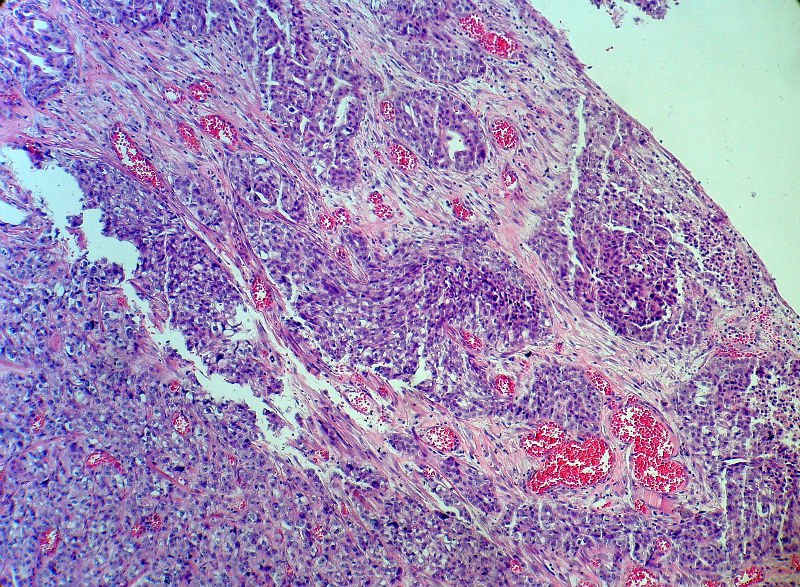

男,82岁,小肠穿孔紧急手术。

大体,小肠一段,长约60厘米,与粘膜面可见三个溃疡型肿物,肠系膜淋巴结肿大。

肿瘤呈巢片状分布,细胞大小相对一致,胞浆丰富,胞核呈细颗粒状,可见小核仁,血管较丰富,考虑神经内分泌肿瘤,加做免疫组化(Ki67、Syn、NSE、CgA、CD56)分级。

肠系膜淋巴结

患者已于术后第二天死亡。